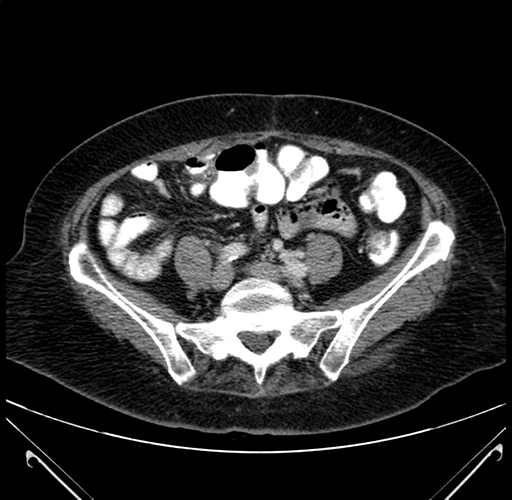

Pre-Chemo: Axial Venous